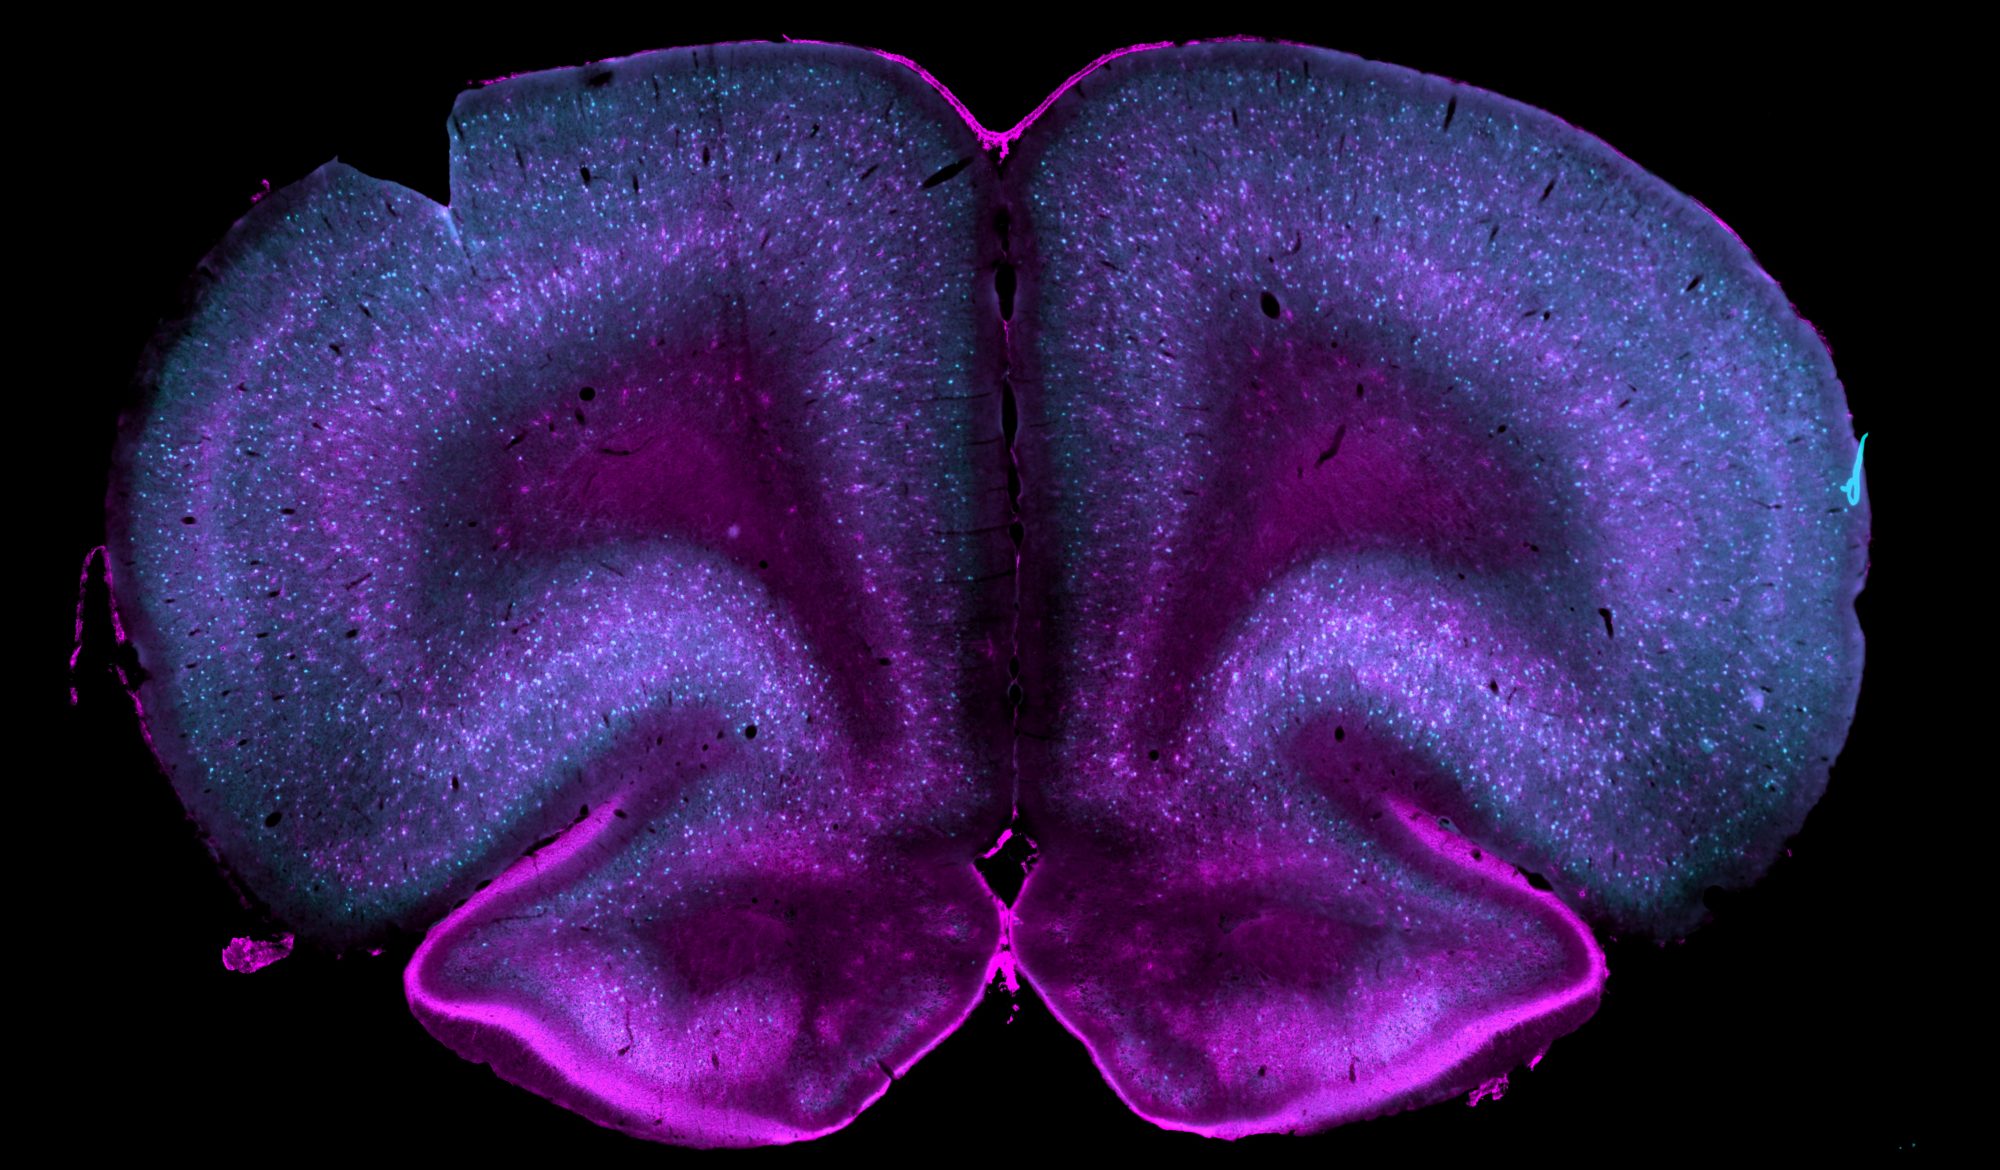

Dr. Gildawie is a behavioral neuroscientist and Assistant Professor of Psychology at Simmons University. Dr. Gildawie is a Simmons alumna and began her work in the field of neuroscience with Dr. Amanda Carey, studying the impact of diet on age-related cognitive decline. She received her PhD from Northeastern University, where she conducted research in the Developmental Neuropsychobiology Laboratory under Dr. Heather Brenhouse, exploring how early life experience affects neurostructural development in the brain. She then went on to hold an IRACDA Postdoctoral Fellowship at Tufts University in the Byrnes-Vassoler Lab. Her research used rodent models to investigate the sex-dependent impacts of prenatal opioid exposure on neurodevelopmental and long-term changes in the brain and subsequent behavior.